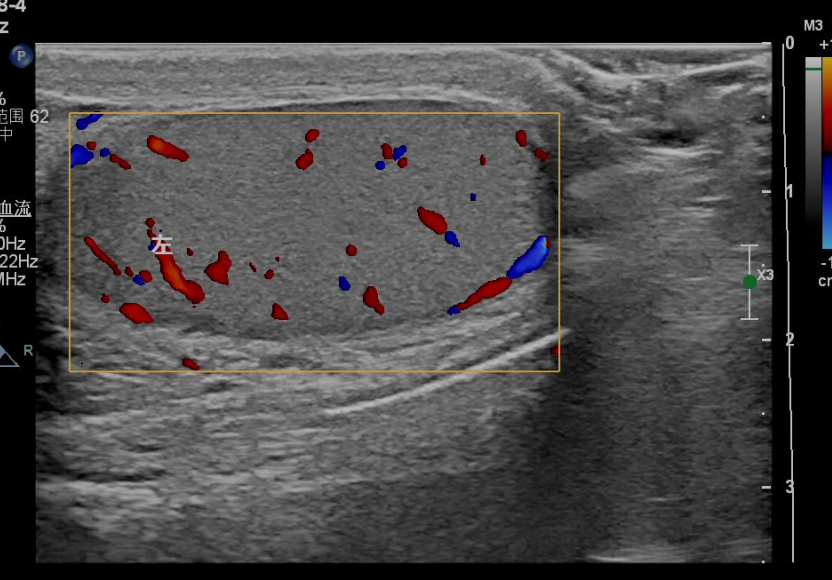

超声影像图像如下:

左侧正常睾丸血流信号图像。

CDFI(彩色多普勒血流成像):看血流,定生死

这是诊断睾丸坏死的核心依据:坏死的睾丸因血液供应完全中断,超声下内部无明显血流信号;而正常睾丸或未完全坏死的睾丸,会显示丰富的血流信号。需要注意的是,扭转的精索包块内可能仍有少量血流,需结合二维超声综合判断,避免误判。